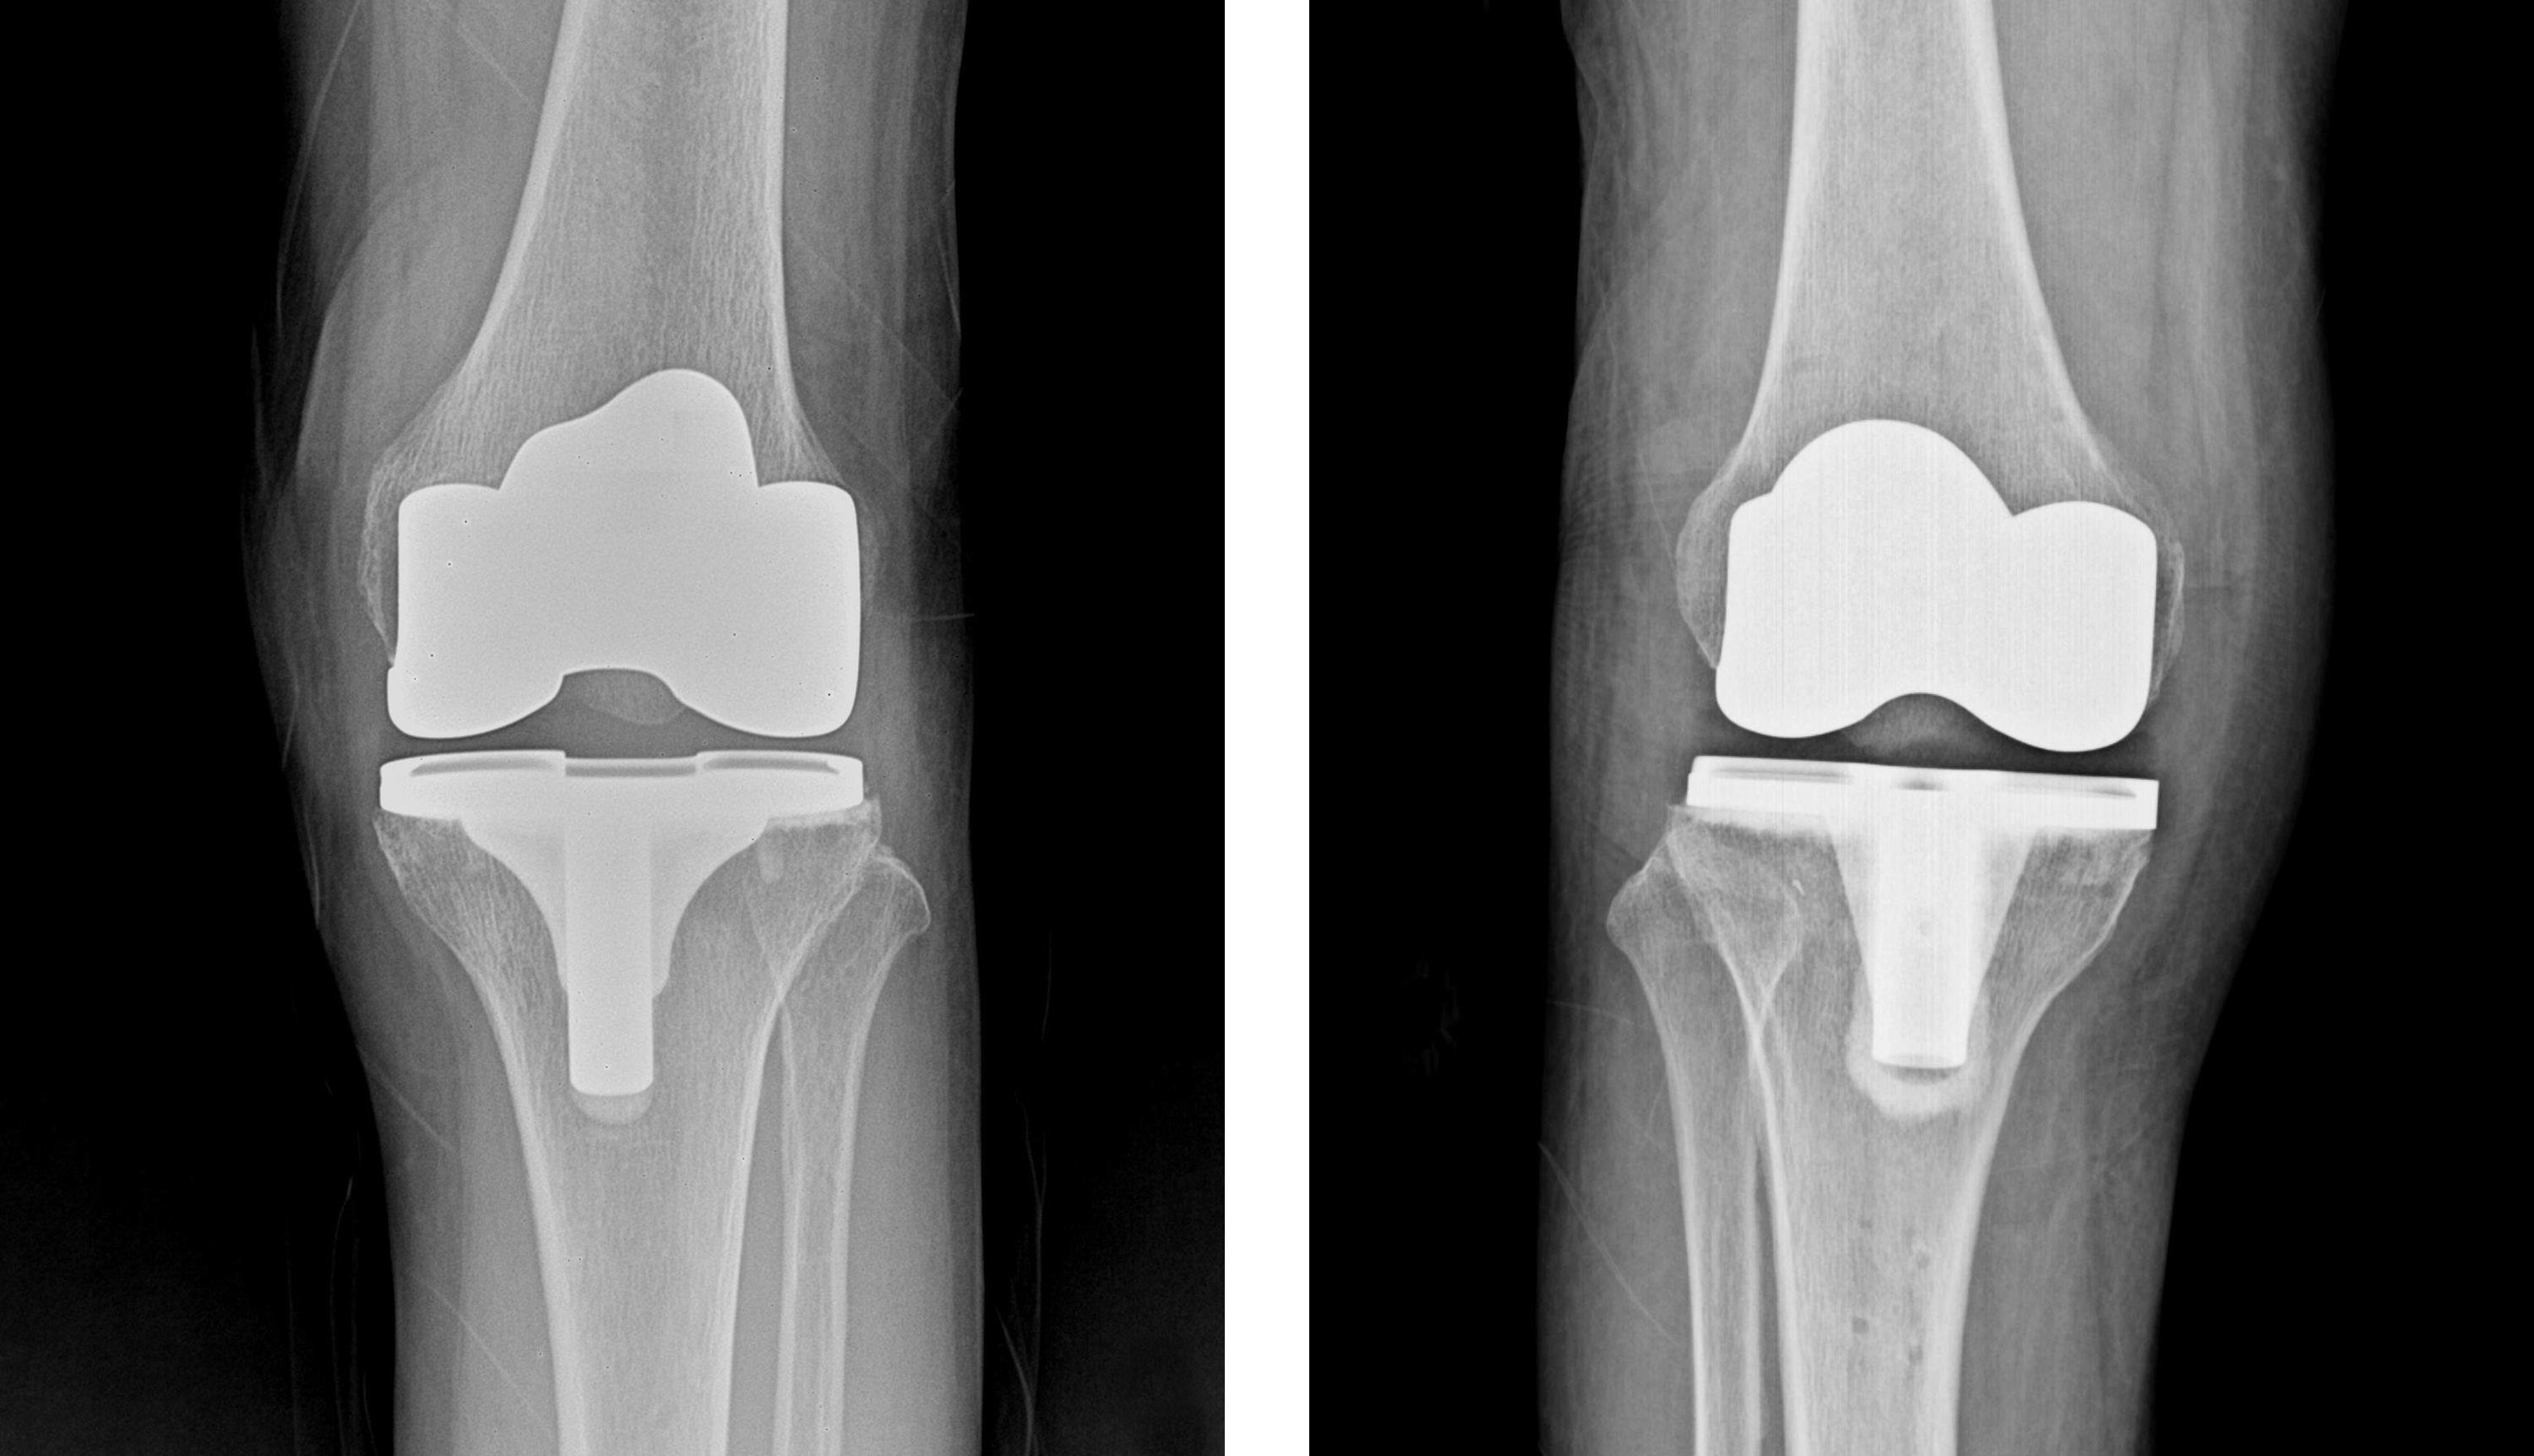

관절 연골 손상이 심한 경우 인공관절수술, 관절내시경수술, 연골판재생술, 절골술, 줄기세포치료술 등의 수술적 치료를 시행합니다.

인공관절수술